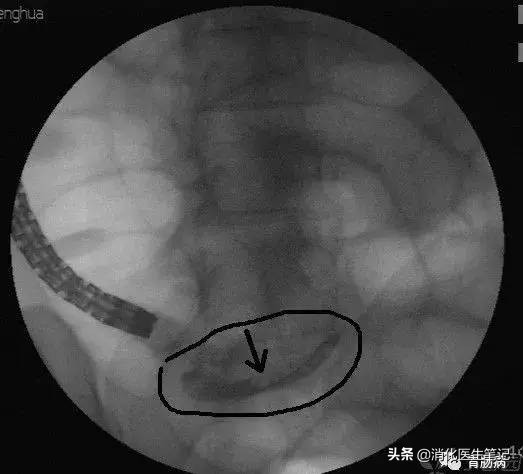

(4)球囊或网篮取石术:通过内镜下置入球囊导管或取石网篮,将粪石取出。(黑箭头示取出的粪石)。